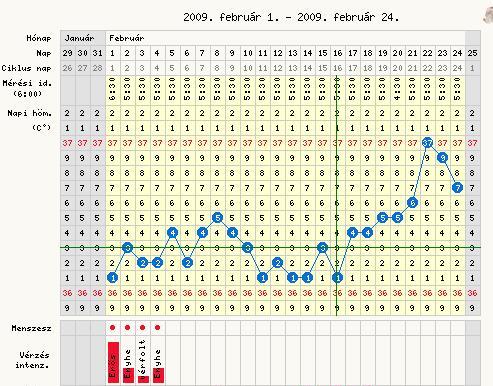

Princzike, szép görbusz!!!